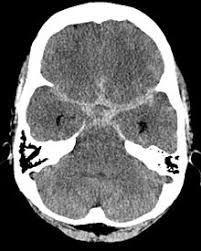

Hirnblutung nach sturz folgeschäden. Innerhalb des Hirngewebes oder zwischen Schädel und Hirn kommt es zu Blutungen die die Funktion der Hirnzellen beeinträchtigen. Deswegen sollte man bei jeder Kopfverletzung vorsorglich einen Arzt aufsuchen. Das kann dann die Ursache für eine massive Schädigung deines Hirngewebes sein.

Somit ist auch ein Absterben von Gehirnzellen bei einer Hirnblutung nicht ausgeschlossen. Meist kommt es im Rahmen eines Schädel-Hirn-Traumas zu mehreren Blutungsformen nebeneinander. Symptome wie Merkschwäche Konzentrationsstörungen Verwirrtheit Wesensveränderungen starke Kopfschmerzen oder ein Druckgefühl weißen auf eine verspätete Gehirnblutung nach einem Sturz hin.

Die Folgen können harmlos aber auch schwerwiegend sein. Die Blutung kann einen Bluterguss erzeugen der immer mehr wächst. Wird er größer steigt auch der Druck in deinem Schädel.

In vielen Fällen entsteht eine Hirnblutung ohne äußerliche Einwirkung im Verlauf einer Erkrankung wie eines Bluthochdrucks eines Aneurysmas Gefäßaussackung oder anderen Gefäßveränderungen. Die Folgen einer Hirnblutung Blutungen im Gehirn können lebensbedrohlich sein und auch zu Schlaganfällen führen.